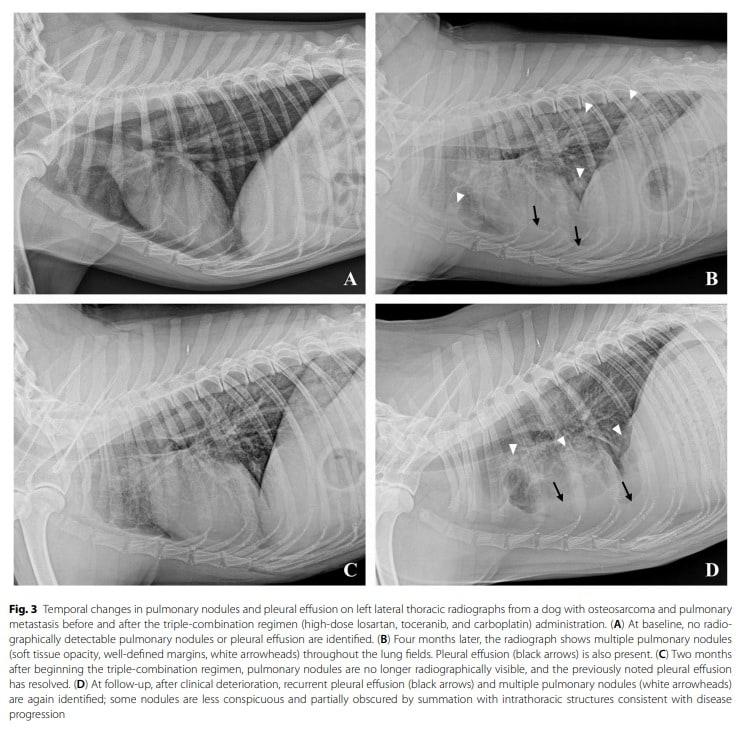

본문 이미지 - 국제학술지 아이리시 베테리너리 저널 갈무리(FM동물메디컬센터 제공) ⓒ 뉴스1

국제학술지 아이리시 베테리너리 저널 갈무리(FM동물메디컬센터 제공) ⓒ 뉴스1